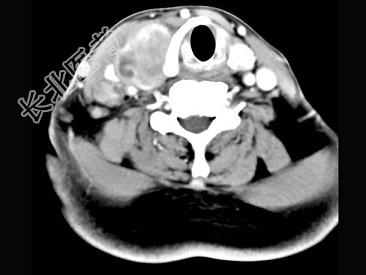

- 多项选择题女,54岁, 右侧颈部肿大近1年,近来病人有声嘶、吞咽困难, CT扫描如图,正确的描述或诊断是 ( )

A、右侧甲状腺肿大,密度减低

B、增强扫描示甲状腺呈不规则强化团块影,其内有低密度区,病灶境界不清

C、右侧颈内静脉增粗,其内可见不规则充盈缺损区

D、甲状腺癌

E、右侧颈内静脉瘤栓形成